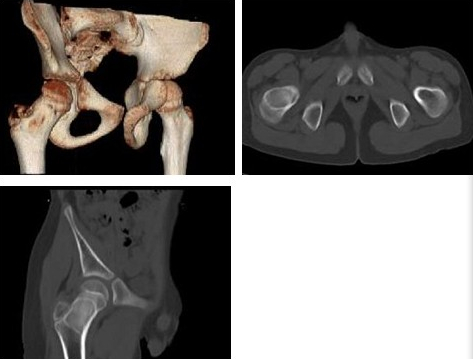

患者女,61岁,今晨从床上不慎摔至地面,右肩部着地,局部剧烈疼痛,患者用左手托住右侧肘部,头部向右侧偏斜,前来就诊。检查结果如下图,可明确诊断为()

A:右肱骨外科颈骨折

B:右肱骨干骨折

C:右肩锁关节脱位

D:右肩关节脱位

E:右锁骨骨折

F:右喙锁韧带断裂

患者,男,14岁,2个月前跌伤右膝部,后感觉疼痛逐渐加剧,肿胀,有时发热,在38℃左右,检查:右膝部肿胀,关节呈屈曲位,不能完全伸直,表面温度升高,有压痛,浮髌试验阴性,最可能的诊断是()